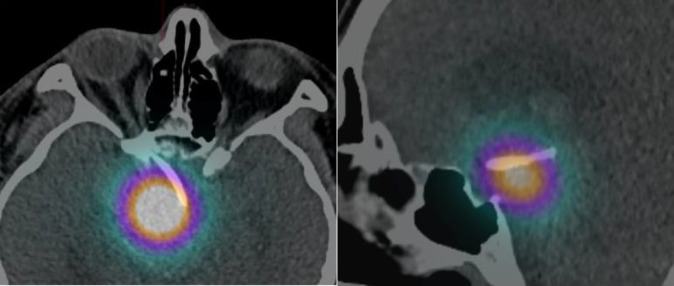

Craniopharyngioma is a rare, benign intracranial tumour that can present with solid, cystic, or mixed solid-cystic characteristics. This case report aims to discuss the follow up assessment of our patient after one year of the irradiation therapy for craniopharyngioma. A 43-year-old male who has underlying refractory cystic craniopharyngioma requiring two-weekly aspirations, complicated with visual impairment and panhypopituitarism, was referred to our department for intra-cavitary irradiation therapy. Initial diagnostic assessment with Tc-99m MAA followed by dose calculation using the Backlund formula were conducted prior to the therapy. The patient received 6.22 mCi (230.14 MBq) of Ytrrium-90 citrate colloid via the Ommaya reservoir to deliver a radiation dose of 300 Gy to the tumour. Positive outcomes were observed as signified by the reduction on the aspirated cystic frequency and volume, tumour volume, improvement on the visual function and stable hormonal level. Despite the complications, the intra-cavitary irradiation therapy has demonstrated a significant and valuable therapeutic option for our patient in the management of refractory cystic craniopharyngioma.